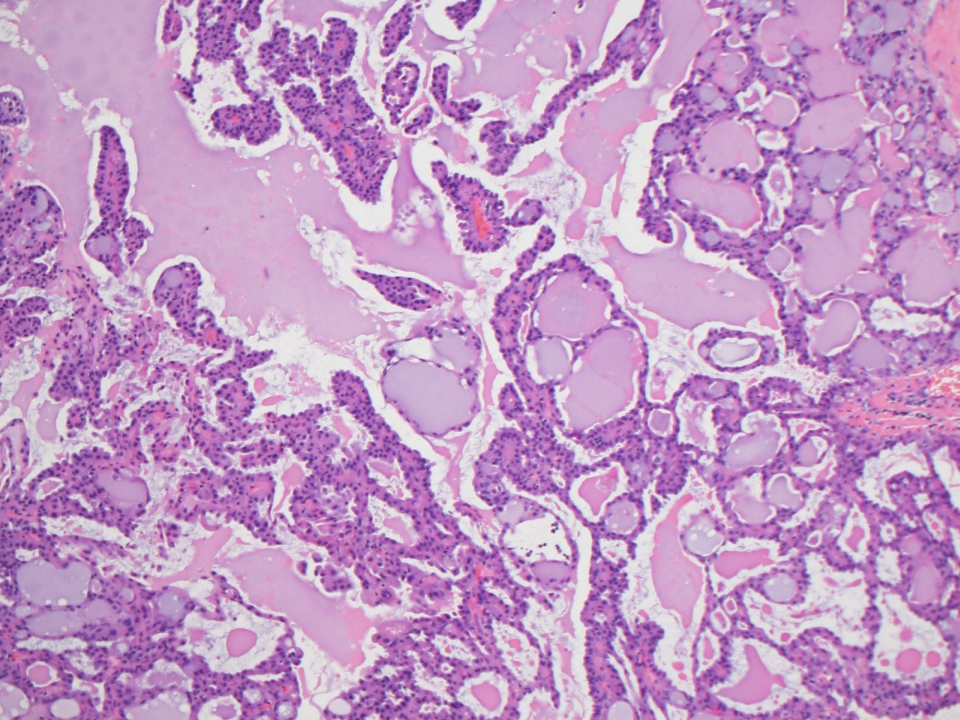

Pineal gland histology pathology outlines. The system is applicable to all invasive carcinomas. Special subtypes of breast carcinoma lobular tubulolobular tubular papillary mucinous cribriform medullary. Ordinary e mails are welcome.